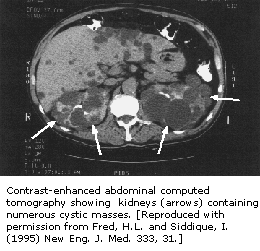

成人多囊肾脏疾病(APKD)是以在一个或两个肾脏中出现大囊、导致慢性肾衰竭为特怔的疾病。肾脏在人体中作用是,过滤血液中以尿和细胞外流动的浓缩氢、钠、钾、磷及其它离子形式出现的代谢最终产物。

1994年欧洲多囊肾脏病协会从染色体16中分离出一种基因,染色体16在具有APCD的家属中遭到破坏。被PKD1基因编码的蛋白质是一种包含细胞-细胞间反应、细胞-基质间反应的整体薄膜蛋白。PKD1在正常细胞中的作用可能与中间微管功能有关,如在薄中放置Na(+),K(+)—ATPase

离子泵。程序性的细胞死亡或细胞凋亡可能也包含在APKD中,进一步搞清楚疾病的发病机制期待做进一步研究。